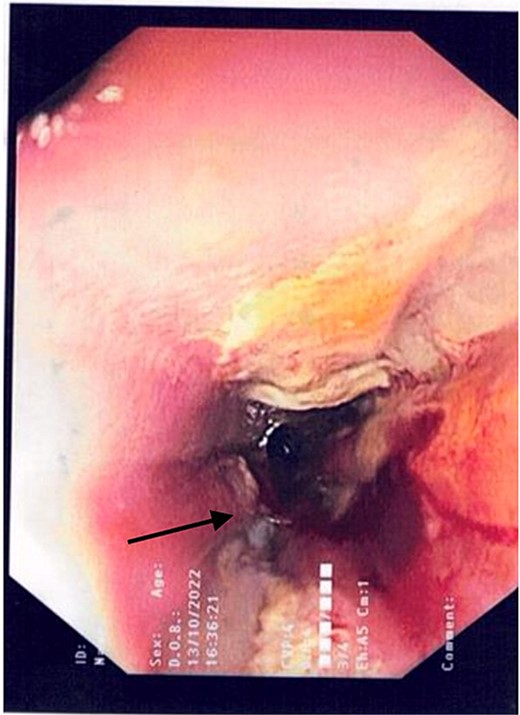

2L of pus was evacuated during laparoscopy, and it was converted to open due to limited views. At this stage, there was no obvious perforation. The entire colon was inspected, following splenic flexure and caecal mobilization. On inspection of the stomach, the wrap was intact with an unremarkable leak test. The decision was made to proceed with gastroscopy, whereby a 3 mm pinhole defect was seen at the GOJ at the 9 o’clock position, as shown in Fig. 2. Three haemostatic Cook Medical Instinct clips were placed, from distal to proximal, ensuring there was stable apposition of the perforated mucosa prior to deploying, as demonstrated in Fig. 3. Following this, the NGT was re-inserted under vision. The midline laparotomy was partially closed and Abthera dressing placed. The patient was taken to ICU intubated, with definitive closure performed 48 h later.

Gastroscopic image demonstrating the successful application of haemostatic clips at the site of perforation (arrow).